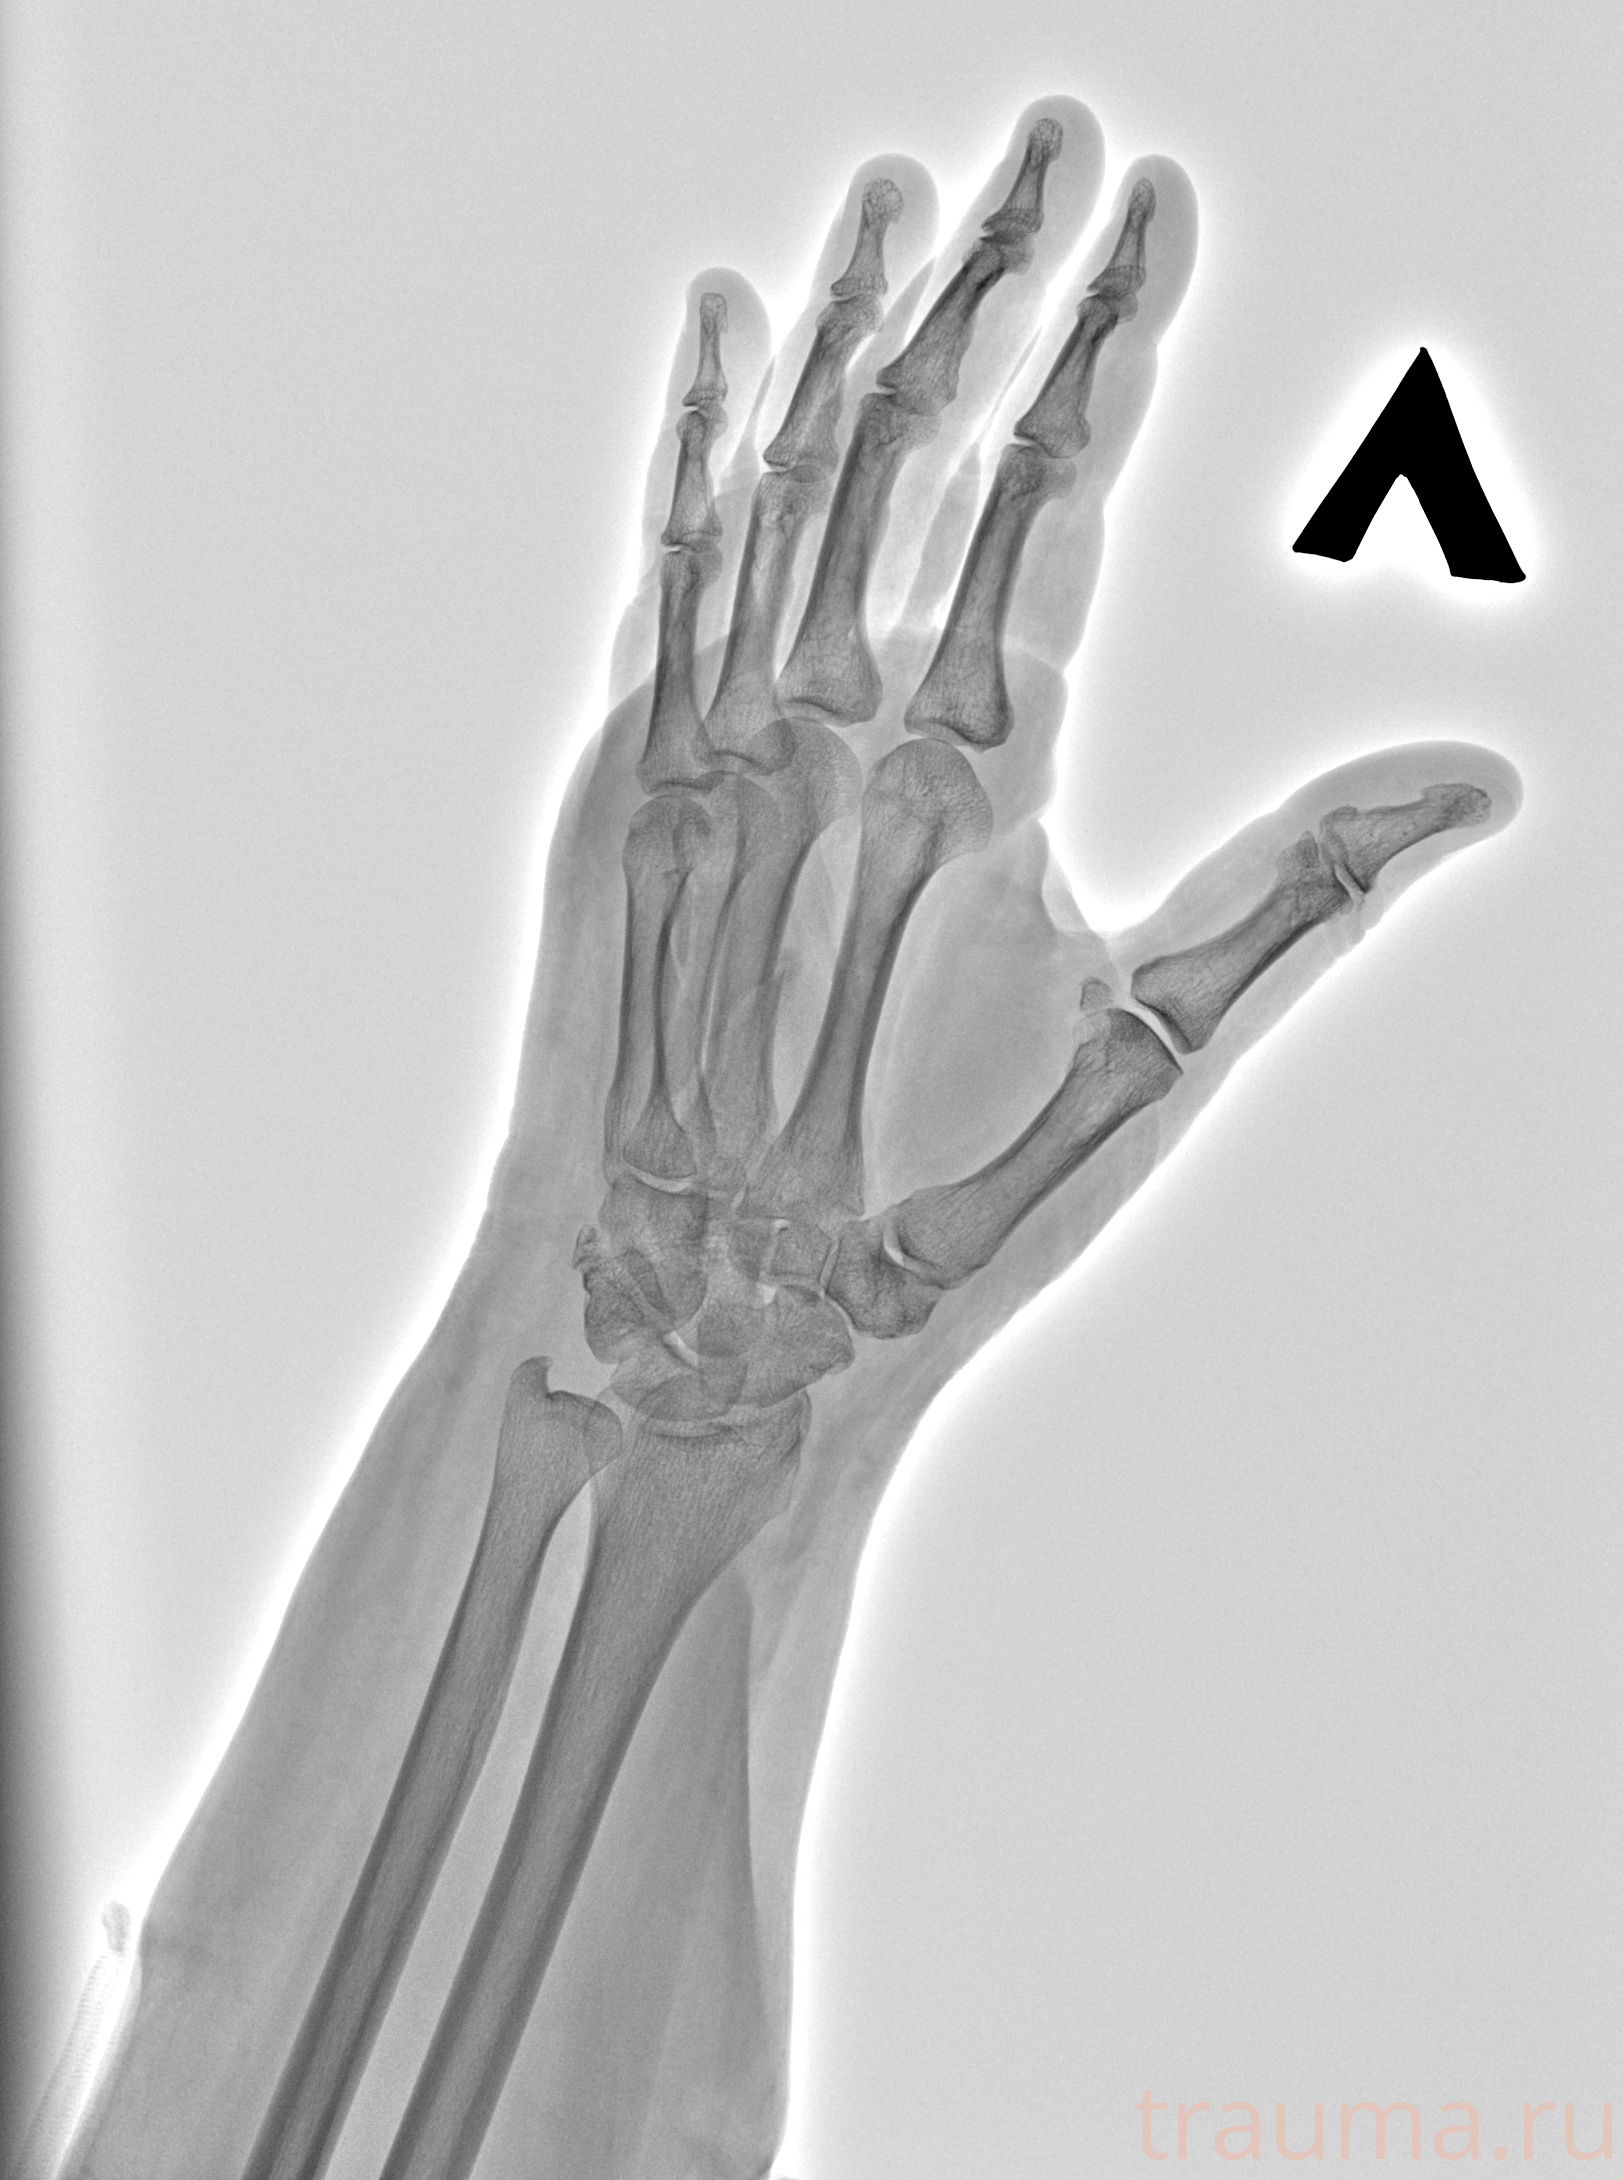

Рентген на дому: по вашему адресу приезжает врач-рентгенолог, травматолог-ортопед с мобильным рентгеновским аппаратом, проводит диагностику травмы или заболевания, делает необходимые рентгенограммы, дает рекомендации по дальнейшему лечению. Получить качественные снимки в домашних условиях возможно благодаря уникальной методике, разработанной МосРентген Центром для института  Склифосовского